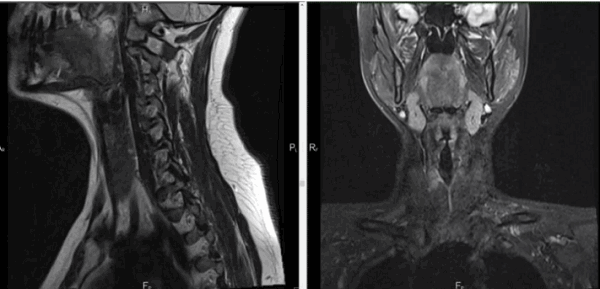

- Это немного разные вещи. МРТ шейного отдела позвоночника - узконаправленное обследование. При выполнении данной процедуры видны только позвоночник и спинной мозг. МРТ мягких тканей шеи - обследование более расширенное. При его проведении просматриваются и оцениваются мышцы, слюнные железы (подъязычная, нижнечелюстная, околоушная), щитовидная железа, пищевод, гортань, а также межфасциальные пространства. Просматривается также корень языка, грушевидные синусы, лимфоузлы, парафарингеальные (окологлоточные) области. Позвоночник и спинной мозг на МРТ шеи тоже видны, но не так детально, как на МРТ шейного отдела позвоночника.

- Пациент ложится на стол томографа и ему выполняется сканирование в трёх проекциях. Специалист в это время управляет аппаратом из соседней комнаты и по необходимости связывается с пациентом посредством двусторонней связи. Данные передаются на монитор, и врач оценивает состояние органов по полученным изображениям. Результаты отражаются в заключении. При необходимости данные могут быть записаны на электронный носитель, который пациент забирает с собой.

Воспалительные заболевания и объемные образования шеи часто встречаются в хирургической практике. Дифференциация патологий вызывает трудности из-за сложной анатомии рассматриваемой области и схожести клинических проявлений. МРТ позволяет получить подробные изображения мягкотканных и костных структур, опираясь на принцип магнитного резонанса. Компьютерная программа преобразует данные в серию срезов и формирует объемную картинку, которую можно увеличивать и рассматривать в любой плоскости. Толщину среза устанавливает врач в зависимости от предполагаемого диагноза, целей и задач исследования.

Магнитно-резонансная томография указанной области, вариант нормы

Стол с пациентом перемещается в тоннель. Сканирование проводят в боковой, прямой и поперечной проекциях. При необходимости реконструируют 3D-модель изучаемой зоны.